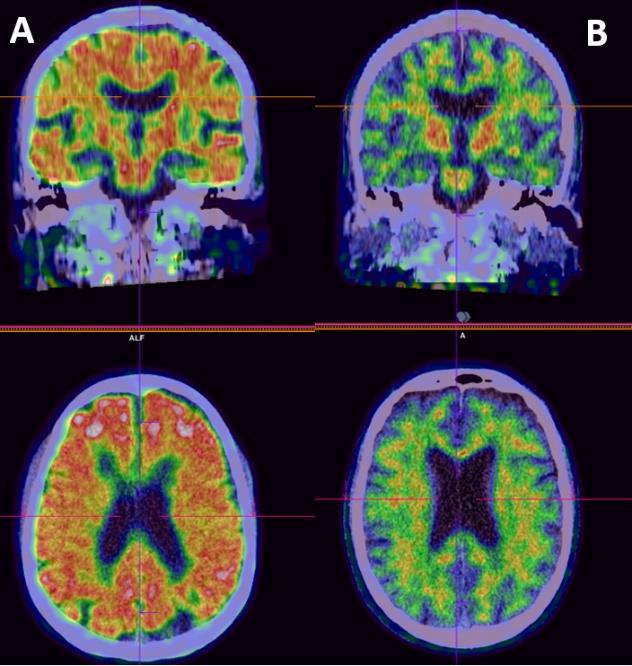

3.2.5.2 Amyloid-bindende radionuklider ved Alzheimers sykdom

Ved mistanke om Alzheimers sykdom er PET-baserte amyloid-bindende radionuklider som 11C-Pittsburgh compound B (PIB), 18F-florbetapir, 18F-florbetaben og 18F-flutemetamol (Figur 5) i bruk for å detektere amyloide plakk i kortikalt parenkym. I Norge er flutemetamol (18F-Flut-PET) tilgjengelig ved flere sentre.

Figur 5. Positronemisjonstomografi (PET) etter injeksjon av radioaktivt merket flutemamol, som bindes til amyloid beta. A = visuelt positive 18F-Flut PET med kortikalt opptak, kan sees ved Alzheimer sykdom; B = visuelt negativ 18F-Flut PET uten kortikalt opptak.